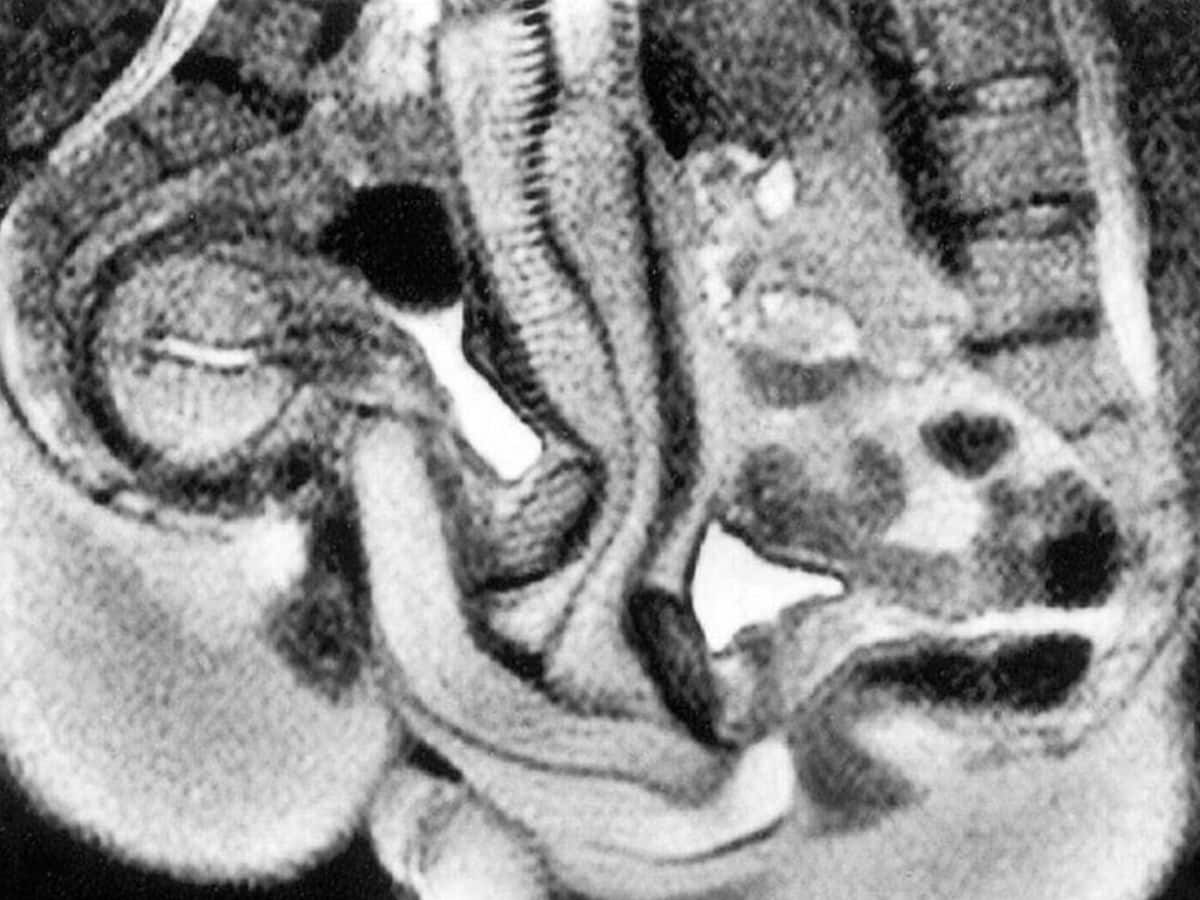

Σύμφωνα με τις μαγνητικές τομογραφίες από το πείραμα, κατά τη διάρκεια της σεξουαλικής επαφής, το ανδρικό μόριο δεν παραμένει ευθύ. Αντιθέτως, καμπυλώνεται προκειμένου να προσαρμόζεται στο σχήμα του γυναικείου κόλπου– σε αντίθεση με όσα υποστήριζαν παλαιότερες θεωρίες, που φτάνουν πίσω στην εποχή του Λεονάρντο ντα Βίντσι.

Η μελέτη διαπίστωσε ότι το πέ:ος λυγίζει σαν μπούμερανγκ κατά τη διάρκεια της πραξης.

Ο κόλ:πος δεν είναι τόσο ευθύς όσο πιστευόταν προηγουμένως πριν από τη μελέτη.